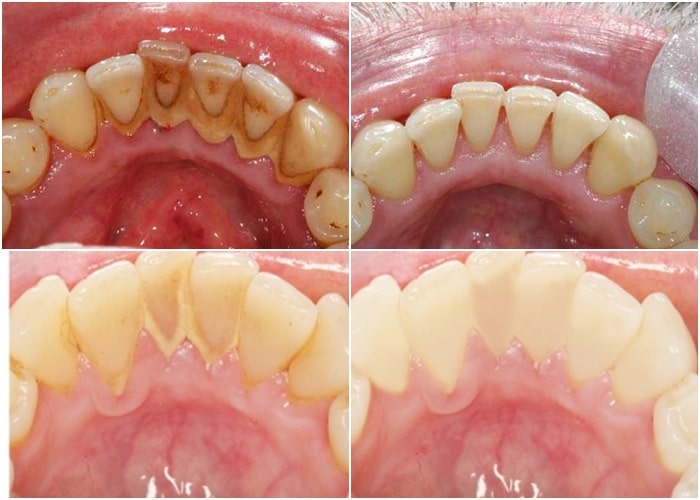

Hình ảnh cao răng bám đầy răng bệnh nhân

- Hạn chế nguy cơ mắc các bệnh lý răng miệng: cao răng là nơi trú ngụ của rất nhiều vi khuẩn có hại – chúng chính là nguyên nhân hàng đầu gây ra các bệnh lý như sâu răng, tụt lợi, viêm nha chu, mòn men răng,…

- Răng trắng sáng hơn: một trong những nguyên nhân khiến răng bị xỉn màu chính là các mảng bám cao răng. Việc loại bỏ cao răng sẽ mang lại một hàm răng sáng bóng và tăng tính thẩm mỹ cho cả khuôn mặt.

- Bảo vệ răng và xương hàm khỏe mạnh: vi khuẩn tích tụ trong cao răng theo thời gian sẽ xâm nhập vào sâu bên trong gây hư hỏng nướu và các tổ chức răng từ đó dẫn đến tiêu xương hàm và khiến răng bị lung lay, nguy hiểm hơn sẽ gây ra tình trạng mất răng hàng loạt.

- Loại bỏ hơi thở có mùi hôi hiệu quả: cao răng tích tụ quá dày sẽ khiến quá trình vệ sinh răng miệng trở nên khó khăn hơn. Vi khuẩn tích tụ nhiều sẽ gây ra mùi hôi khó chịu ở khoang miệng. Vì thế, để giữ được hơi thở luôn thơm tho, hãy loại bỏ các mảng bám cao răng.